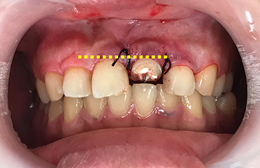

歯茎の線に左右差がないので、外科的に埋まっている根っこ(歯根)を出してしまうと審美的問題が起きてしまいます。

根っこ(歯根)が歯茎の中にあり、このままでは差し歯に出来ない状態です。

歯茎を隣の歯と合わせ審美的な点からも治療し、差し歯に出来るようにしました。